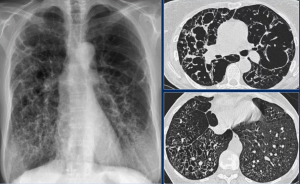

Всем пациентам с подозрением на ГП рекомендуется проведение КТ органов грудной полости для определения характера изменений в легочной ткани, подтверждения диагноза ГП и дифференциальной диагностики с другими ИЗЛ. Различные комбинации рентгенологических признаков формирует КТ картину (паттерн) ГП. В настоящее время принять выделять три основных КТ картины ГП - типичная, вероятная, неопределенная, которые различаются при нефибротиче- ском и фибротическом фенотипах.

Типичная картина нефибротического ГП включает такие изменения легочной паренхимы, как матовое стекло, мозаичная плотность легочной ткани, а также признаки патологических изменений со стороны мелких дыхательных путей (плохо очерченные центрилобулярные очаги, воздушные ловушки).

Типичная картина фибротического ГП включает характерные признаки ГП и признаки фиброза легочной ткани: ретикулярные изменения, нарушающие легочную архитектонику (нормальное расположение сосудов и видимых бронхов) и/или тракционные бронхо- эктазы; +/- сотовое легкое; хаотичное распределение фиброзных изменений (без отчетливого преобладания) или преобладание в средней легочной зоне (на уровне корней), характерна большая воздушность нижних легочных зонСаркоидоз - системное воспалительное заболевание неизвестной этиологии, характеризующееся образованием нека- зеифицирующихся гранулем, мультисистемным поражением различных органов и активацией Т-клеток в месте гранулематозного воспаления с высвобождением различных хемокинов и цитокинов.